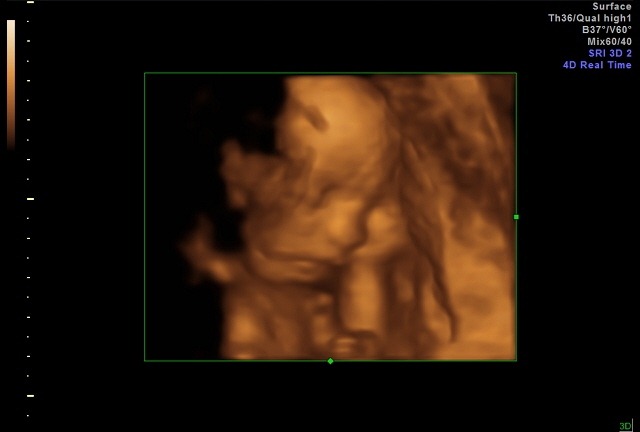

Check out this 4D picture we got this week too! The baby has its cute little hand up next to its cheek!! Aweee!!! ![]()